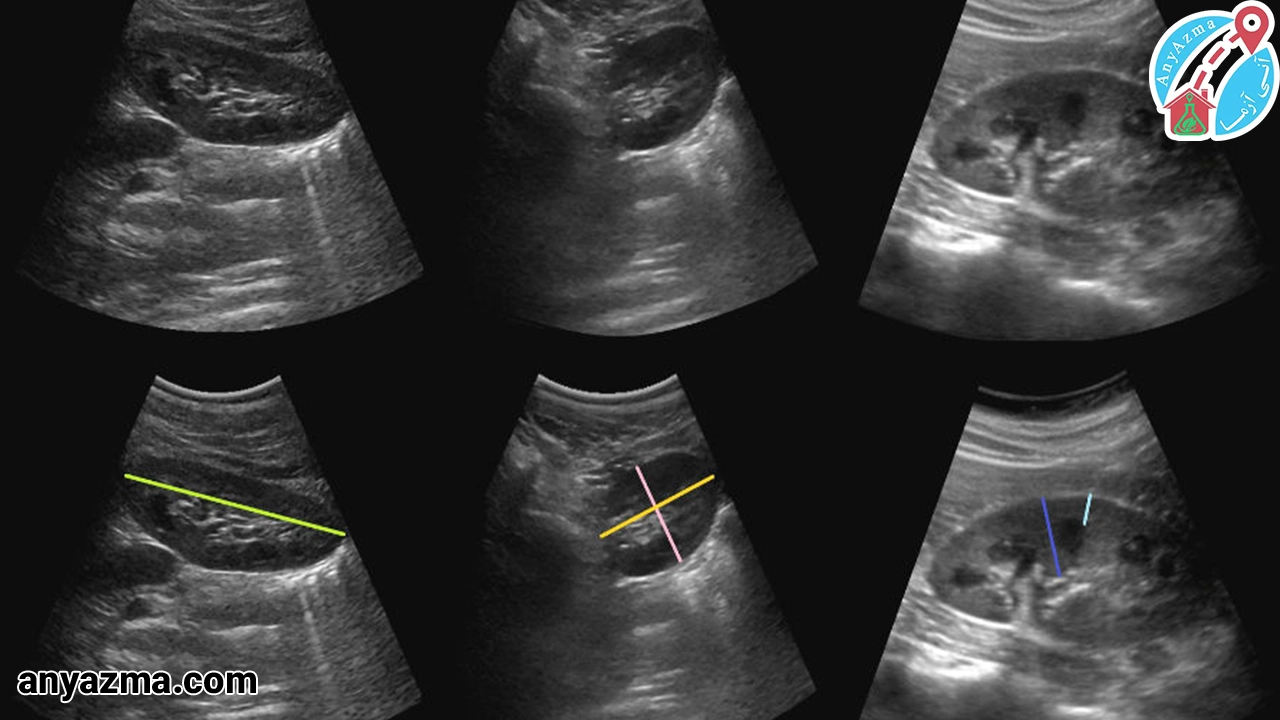

سونوگرافی شکم و لگن

این نوع سونوگرافی در منزل برای بررسی اندامهای داخلی شکم و لگن مانند کبد، کلیهها، طحال، پانکراس، مثانه و رحم استفاده میشود. برای بررسی درد شکم و لگن، تشخیص سنگهای کلیه و کیسه صفرا، و بررسی تومورهای احتمالی کاربرد دارد و جزئیات دقیقی از این اندامها ارائه میدهد. سونوگرافی شکم و لگن، اغلب برای تشخیص علت درد شکمی، ارزیابی سایز و ساختار اندامهای داخلی، و بررسی وجود هرگونه توده یا ناهنجاری استفاده میشود.